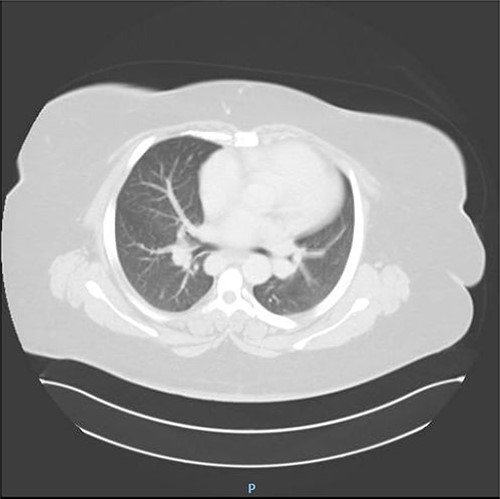

The patient underwent complete preoperative workup which includes clinical history, physical examination, complete blood count (CBC), coagulation profile, chemistry, lipid profile, endocrinology tests, US abdomen, chest X-ray, transthoracic echocardiography, computed tomography (CT) chest and CT abdomen, which showed reversal of intra-abdominal organs as shown in Figs 1, 2 and 3.

CT abdomen showing reversal of intra-abdominal organs with polysplenia.